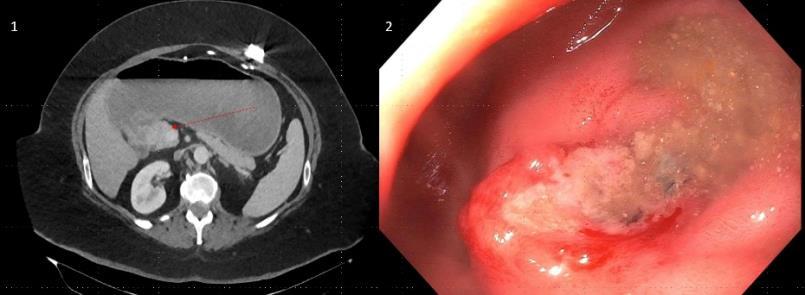

CASE PRESENTATION: A 67-year-old male with a history of partial liver resection, peptic ulcer disease, and Helicobacter pylori gastritis s/p quadruple therapy presented with acute on chronic abdominal pain despite being on a proton pump inhibitor (PPI). He had abdominal pain for the past 5 years associated with nausea, vomiting, diarrhea, and a 50-pound unintentional weight loss. An esophagogastroduodenoscopy (EGD) six months ago demonstrated peptic ulcer disease and Helicobacter pylori which was successfully eradicated.

He underwent a CT-abdomen/pelvis with intravenous contrast in the emergency department which revealed an enhancing 3.4 cm mass in the head of the pancreas with retroperitoneal lymphadenopathy. MRI of the abdomen confirmed the presence of a 3.2 cm enhancing pancreatic head mass with direct extension into the second portion of the duodenum and multiple enlarged retroperitoneal lymph nodes. EGD was remarkable for edema and granularity in the first portion of the duodenum. Endoscopic ultrasound (EUS) was notable for a hypoechoic and heterogeneous irregular mass in the pancreatic head measuring 25 mm by 23 mm in maximal crosssectional diameter with invasion into the serosa and muscularis mucosa of the duodenum. Fine needle aspiration of the pancreatic mass for cytology revealed a well-differentiated pancreatic neuroendocrine tumor (Ki-67 index <1%). Gastrin levels were ordered. He presented again to the hospital 3 weeks later with worsening epigastric abdominal pain and nausea despite adhering to PPI therapy. CT-abdomen revealed new proximal duodenal ulcerations. Gastrin level from the prior admission was noted to be 1988 pg/mL. He subsequently underwent a Whipple's procedure with no complications and was discharged home with a planned EGD surveillance in 6 months.

CONCLUSION: Establishing a diagnosis of ZE can be difficult due to the lack of consistent diagnostic criteria, the widespread use of PPIs that masks mask the symptoms and limited access to gastric pH testing. In our case, the diagnosis was based on a fasting serum gastrin level, FNA results, and imaging findings. Owing to its variable clinical presentation, high mortality, and challenging primary lesion identification, clinicians should consider ZE in the differential diagnosis of patients who are symptomatic despite taking PPI, having Helicobacter pylori successfully eradicated or having multiple duodenal and gastric ulcers that fail to respond to therapy.

Figure 1: CT Abdomen and Pelvis with contrast showing a suspicious mass in the second portion of the duodenum/pancreatic head.